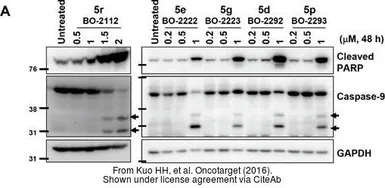

The data was published in the journal Oncotarget in 2016. PMID: 27191263

The data was published in the journal Oncotarget in 2016. PMID: 27191263